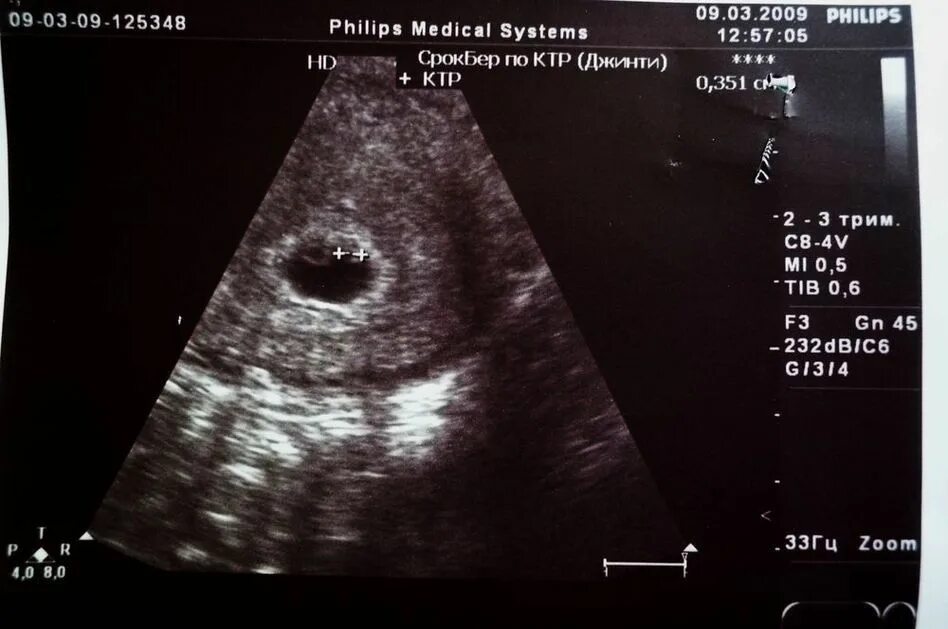

Тянет живот 3 недели